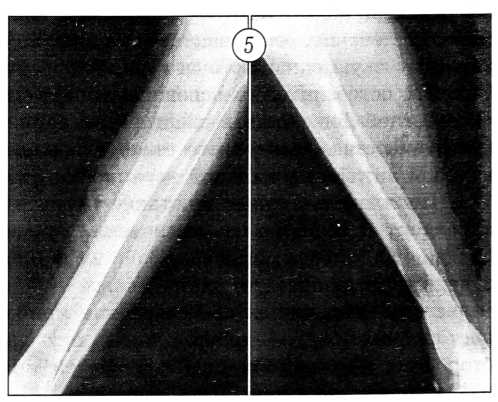

Удалось получить регенераты на двух уровнях: в верхней трети 8 см, в нижней трети 6 см. Аппараты сняты. Фиксация бедра продолжалась 10 мес, голени — 14 мес (рис. 4, 5). Проводились занятия лечебной физкультурой.

Рис. 4. Тот же больной. Сросшийся перелом левого бедра через 10 мес после операции.

Рис. 5. Тот же больной. Рентгенограммы левой голени после компенсации укорочения.